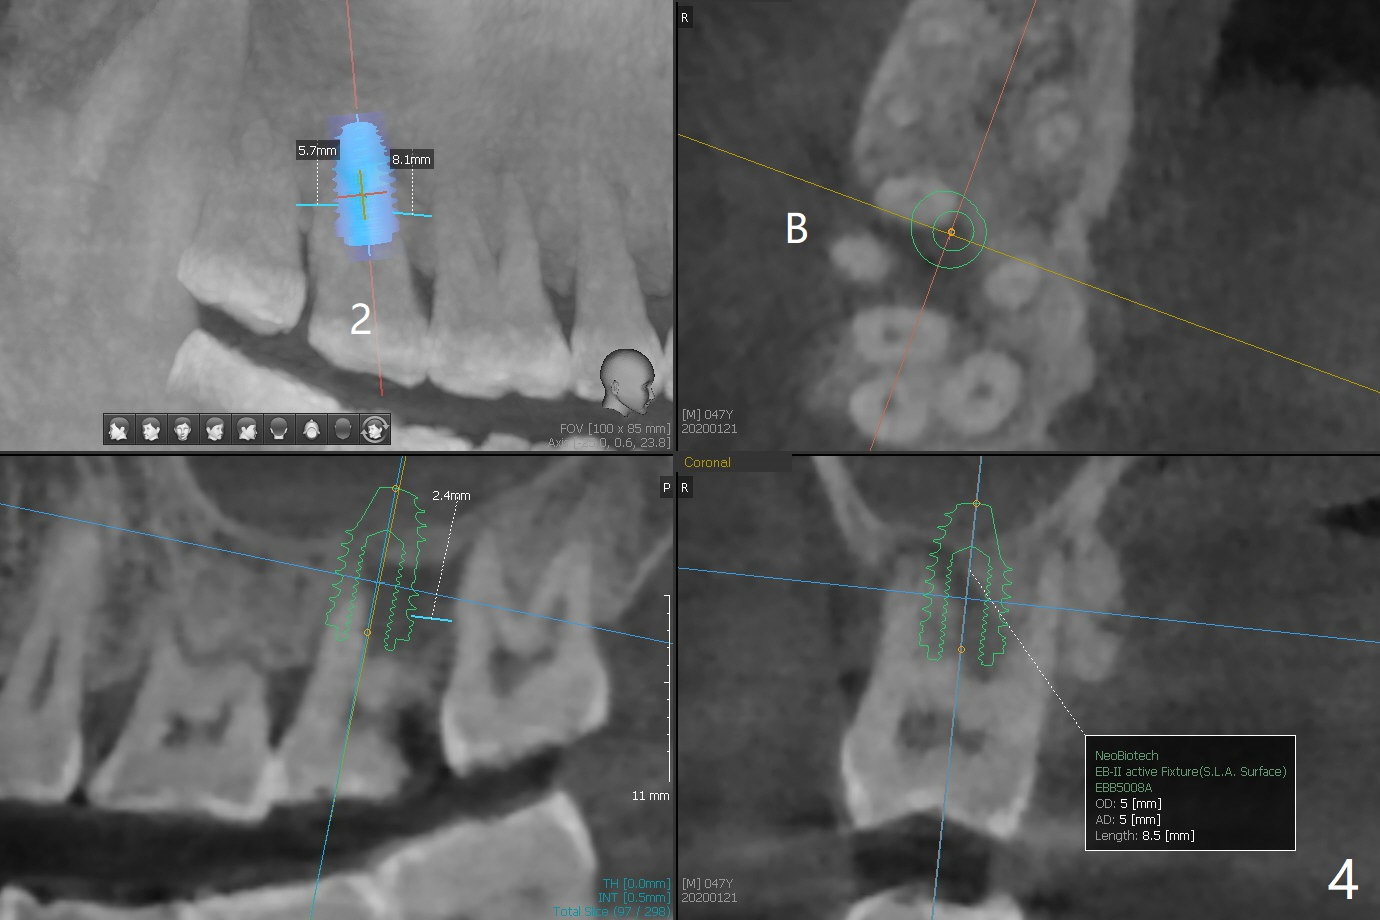

A 47-year-old man has pain at #2 and 15, while #14 has mesiolingual subgingival fracture (Fig.1). #2 is deemed non-salvageable by an endodontist, whereas RCT is finished at #15. When the patient returns for restoration, he reports that the filling is out at #15. In fact it has subcrestal fracture (Fig.2), while #14 equicrestal and difficult to restore (Fig.3). Although the patient agrees to have implants at #2 and 15, DB bone loss at #2 makes it difficult for implant (Fig.4). Use FC implant for primary stability. Insert a small piece of cotton pellet or healing screw and pack sticky bone around the implant before placing a temporary abutment. The latter will form a large gingival cuff, which makes it easy to place pair abutment without interference from the crestal bone. Screw loosening will be reduced. In fact there is PARL of the palatal root of #14 (Fig.5). A FC implant will be also placed at #15 for the same reason (Fig.6).